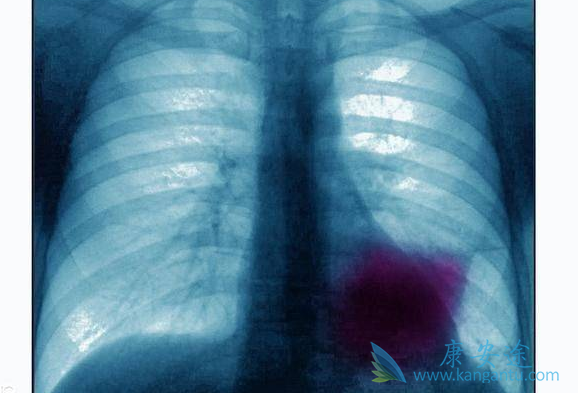

晚期肺癌患者,不论身体还是心里都承受着巨大的痛苦。这时候很多家属会把希望寄托在放化疗上,其实对于晚期肺癌患者来说,由于免疫力的下降,身体的各项机能往往很难承受住长期的放化疗。即使能够一时间摘除病灶,但是复发和转移的可能性也非常高。那么肺癌晚期到底能不能彻底治愈呢?癌症是由恶性肿瘤引起的机体功能性疾病,肿瘤的形成是因为癌细胞的聚集导致。癌细胞是人体新陈代谢所产生的一种非正常细胞,正常人体每天会产生上千个癌细胞,但是因为人体免疫系统的运转,癌细胞会被清除。

当人体的免疫系统出现问题,无法彻底清除癌细胞时,肿瘤就会产生。其次,肺部作为人体五脏之华表,一旦发生癌变则会影响整个人体的新陈代谢,而且肺癌极其容易发生转移。肺癌晚期患者手术的风险极高,而且复发的可能性也极大。所以现在医学界普遍对肺癌进行保守治疗,对肿瘤进行控制,防止其转移扩张。只要肿瘤的活性能够被压制,可以保持相对静止状态,并且能够通过药物减少患者的生理痛苦,即使肿瘤无法清除,也不会危及患者生命,这就是医学界提倡的“带瘤生存”。